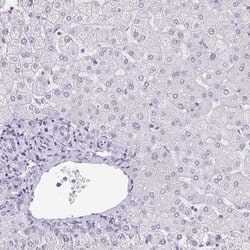

| Immunohistochemistry (Paraffin), Immunocytochemistry | |